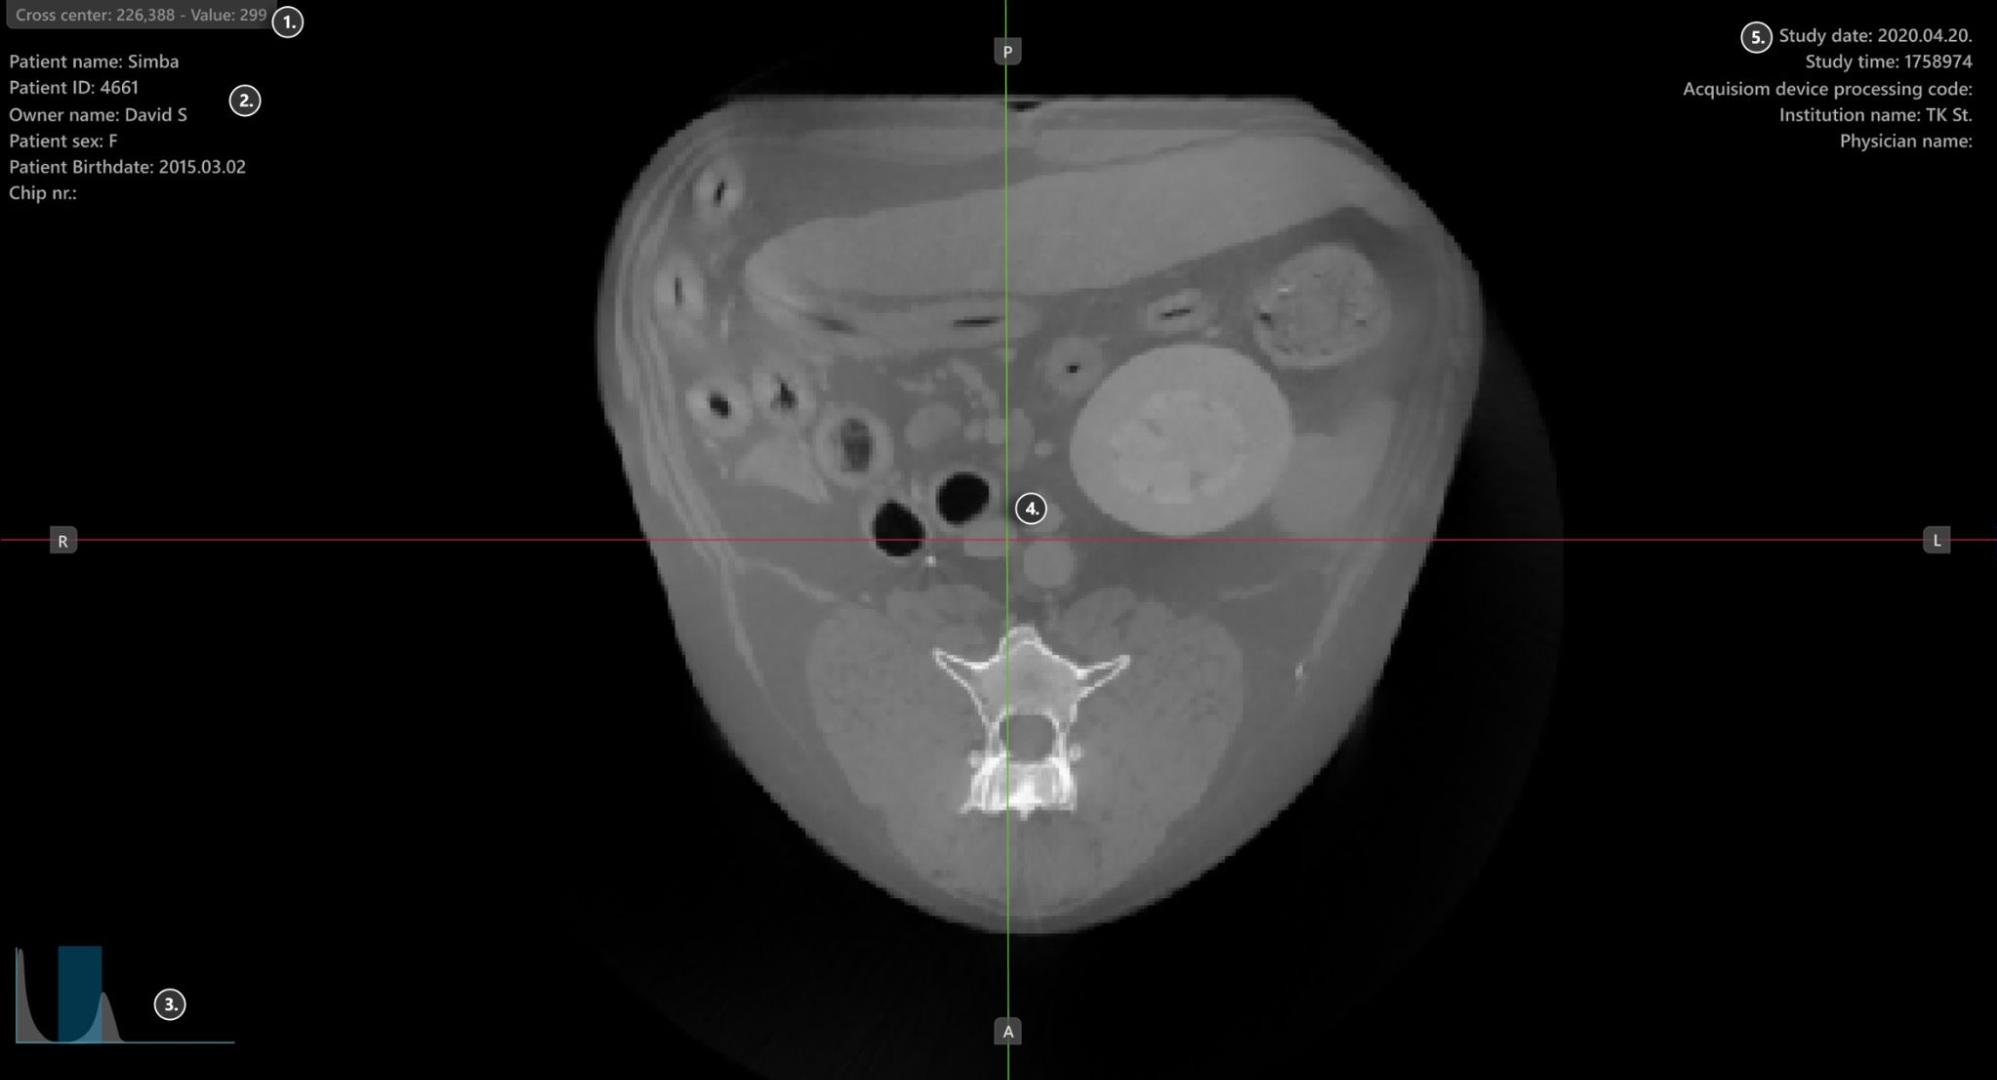

A VisioVIEW CT Megjelenítő szakaszai¶

A VisioVIEW CT Megjelenítő több szakaszból áll, amelyek mindegyike egy adott célra szolgál. Az alábbiakban az egyes szakaszok részletes leírása található.

Megjelenítő terület¶

HU (Hounsfield-egység) pixelérték

Betegadatok

Ablakolási hisztogram eszköz

Szeletelők

Vizsgálati információk